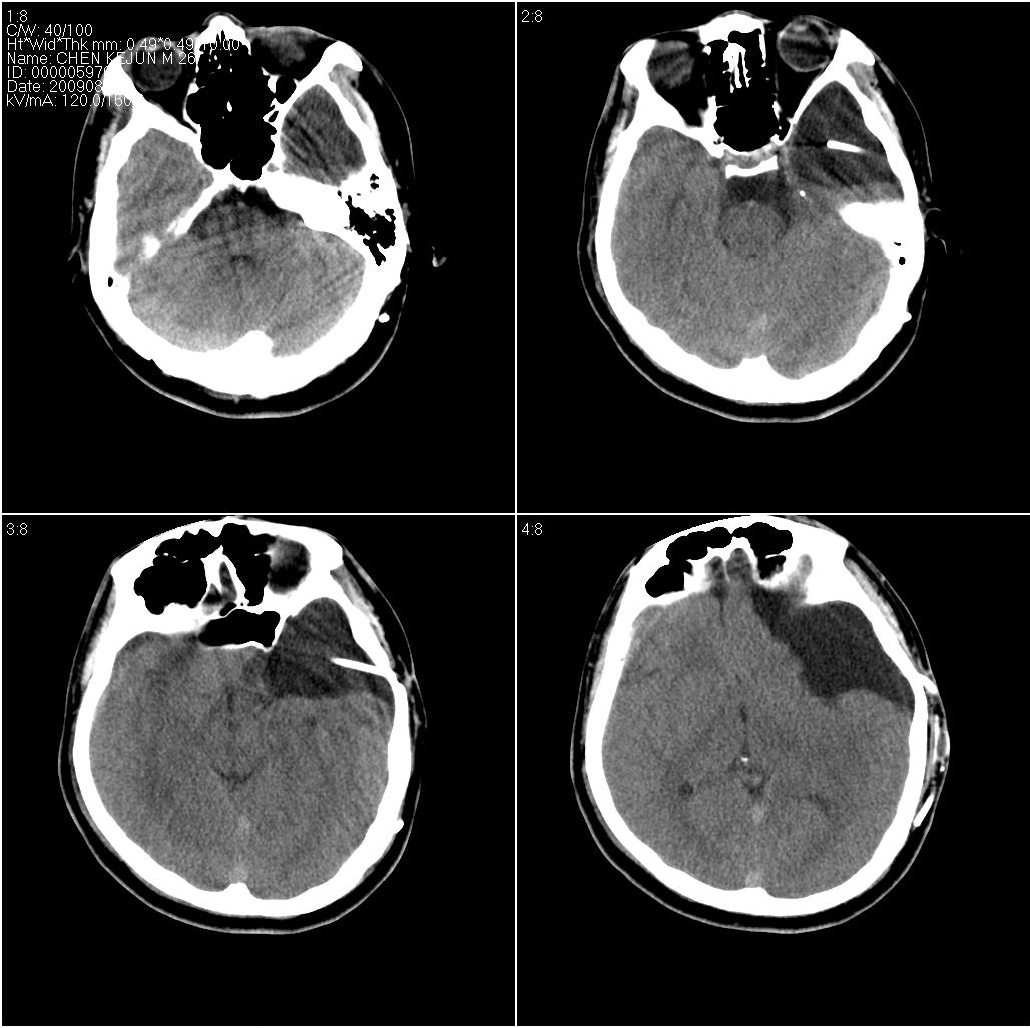

以下是引用随光逐影在2009-8-1 17:07:00的发言:[br]左侧中颅窝及左侧额颞顶部蛛网膜囊肿,并囊液引流术后。

以下是引用hhcckk在2009-8-1 17:29:00的发言:[br]左侧额颞部囊状低密度影,边缘平直,有明显占位效应,考虑蛛网膜囊肿,病变导致左额颞部受压,精神症状可与此有关,李松年编的ct诊断学上有过介绍,额叶联合区损害可引起智力、性格、精神症状,也就是9、10、11区[br][br]